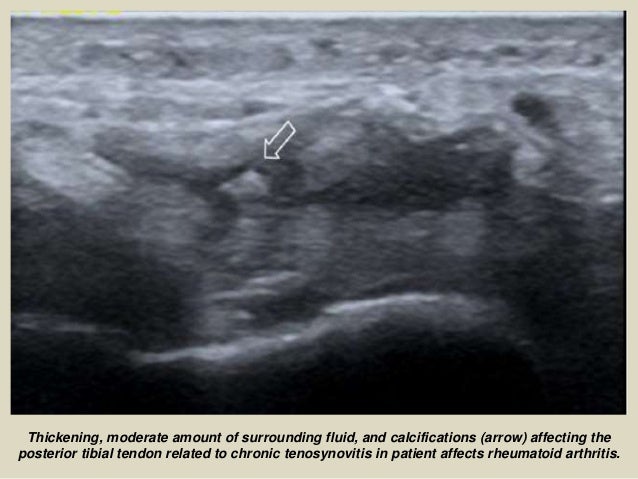

Thickening, moderate amount of surrounding fluid, and calcifications (arrow) affecting the

posterior tibial tendon related...

52. 52. Thickening, moderate amount of fluid surrounding, calcifications and hyperemia affecting the sheath and the posterior tibial tendon related to chronic tenosynovitis in patient affects rheumatoid arthritis.

53. 53. Thickening, moderate amount of surrounding fluid, and calcifications (arrow) affecting the posterior tibial tendon related to chronic tenosynovitis in patient affects rheumatoid arthritis.